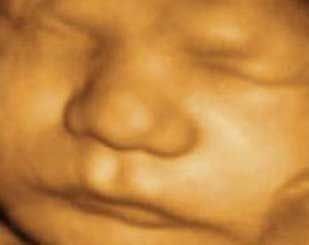

Especialista en ginecología y obstetricia

El centro ginecológico ubicado en la localidad de Andújar, está integrado por el Dr. D. Manuel Muñoz Suárez, doctor en medicina y cirugía, especialista en ginecología y obstetricia con más de 25 años de experiencia en la atención integral de la mujer.